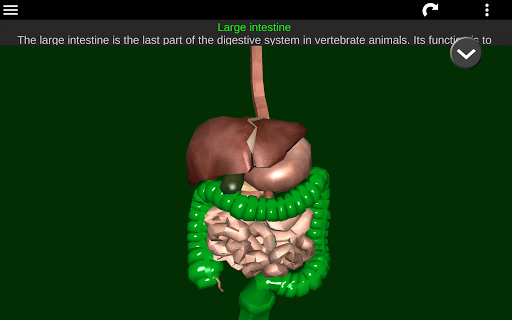

* Digestive system, including the stomach, small intestine, large intestine, and an animation of this system.